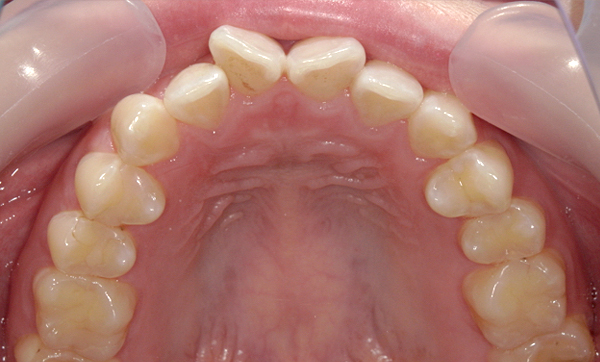

症例_002 前歯「八の字/V字型」症例

治療期間:8ヶ月金額:30万円+税20代女性八の字/V字型上の前歯だけ

| Before | After |